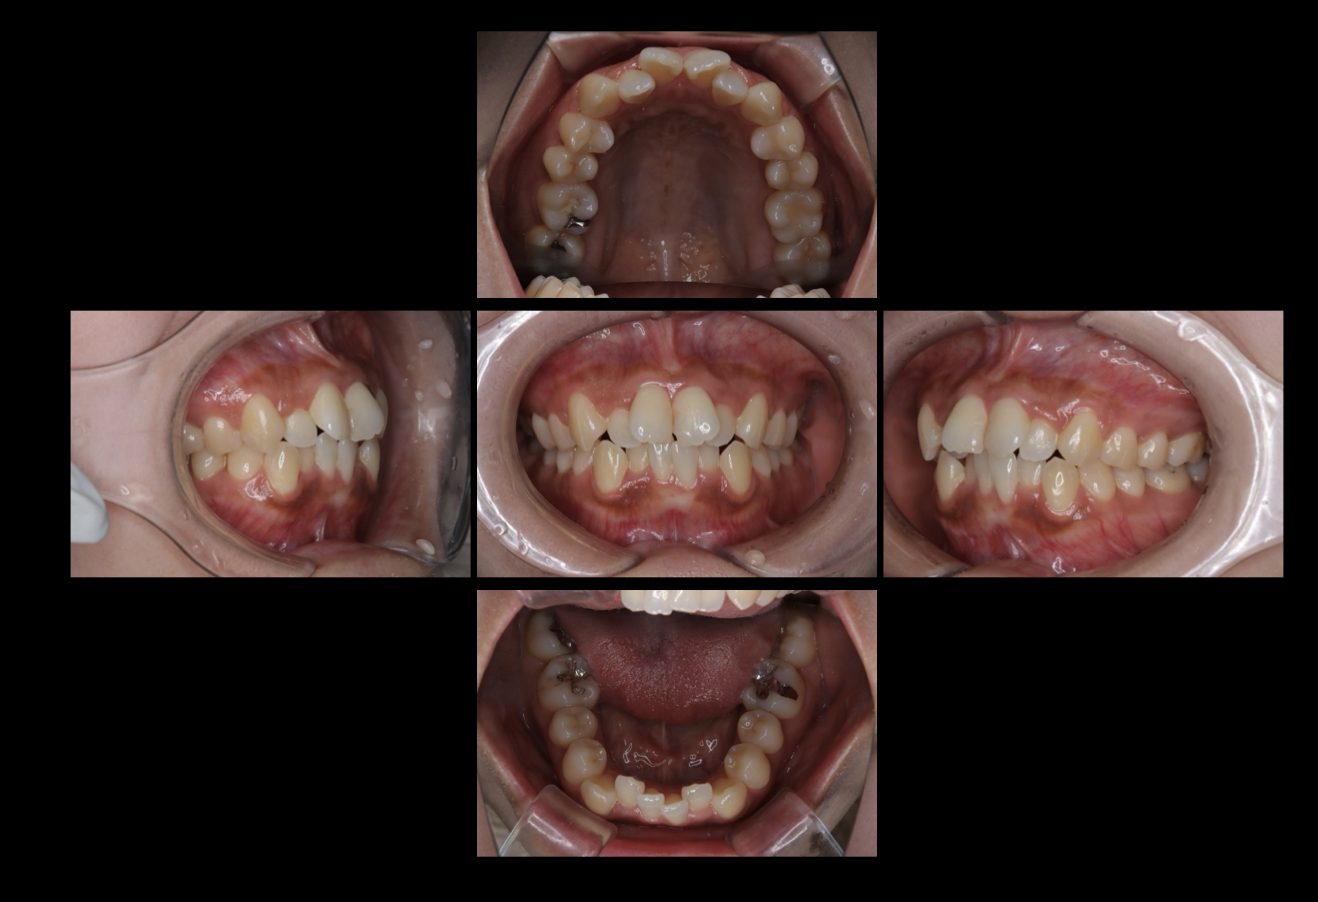

初診時の口腔内及びスマイル写真です。

中等度の歯列不正と前歯の正中の傾きがあります。